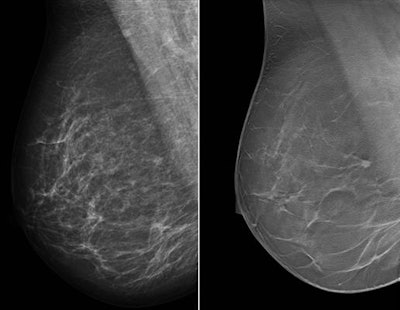

Single-view right MLO mammogram and corresponding DBT slice show the improvement in cancer visibility that can be achieved with tomosynthesis. There is a small cancer visible in the DBT slice just before the pectoral. The lesion is barely recognizable on the concurrent mammogram. All images courtesy of study co-author Dr. Ritse Mann.Wide-angle DBT